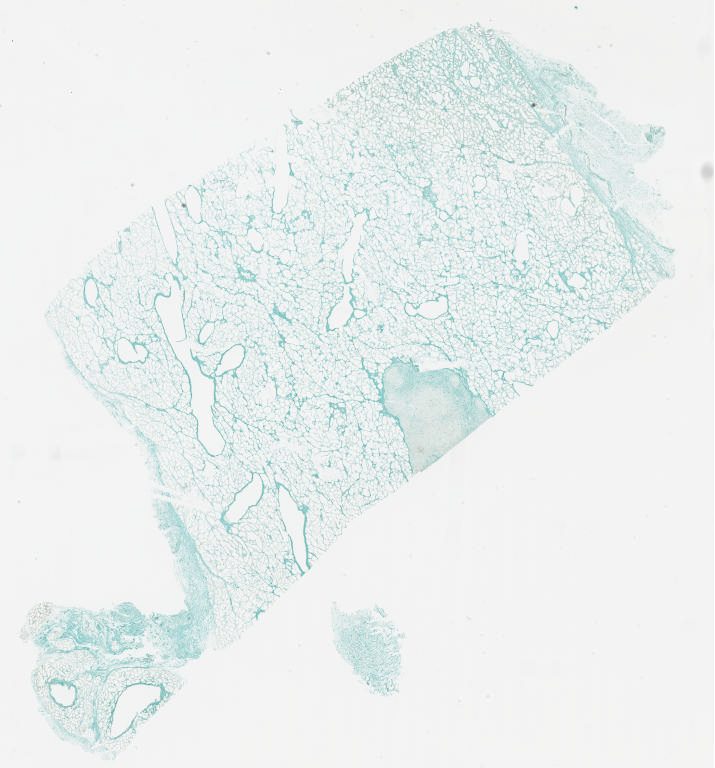

moc2 amxt cddp tunel.svs

moc2 amxt tunel.svs

moc2 cddp tunel.svs

moc2 control tunel.svs

Tunel control.svs